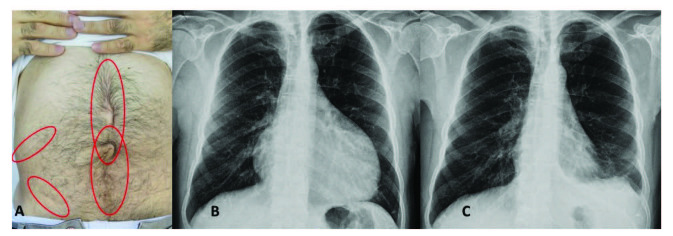

腹膜發(fā)作開(kāi)始局限并迅速蔓延至整個(gè)腹部。腹膜炎癥會(huì)導(dǎo)致典型的腸梗阻癥狀,患者會(huì)遭受嚴(yán)重的胃痛。體格檢查顯示腹部肌肉僵硬、反跳痛和腸鳴音消失——臨床上這種緊急情況與急腹癥的手術(shù)原因無(wú)法區(qū)分。因此,隱匿性腹部手術(shù)史在良性陣發(fā)性腹膜炎患者中很常見(jiàn)(圖 1A)。在疑似病例中,影像學(xué)檢查可能有助于排除手術(shù)病理。腹部發(fā)作后可能會(huì)出現(xiàn)輕度反彈性腹瀉。盡管有戲劇性的表現(xiàn),但腹膜炎的所有體征和癥狀在 24-72 小時(shí)內(nèi)有效消退,沒(méi)有后遺癥,盡管慢性腹水和腹膜粘連的報(bào)道很少。

包含圖片、插圖等的外部文件。對(duì)象名稱為 turkjmedsci-50-1591-fig001.jpg

圖1:(A) 一位因多次腹部手術(shù)而留下疤痕的患者,(B) 胸部 X 光片顯示大量心包積液,(C) 同一患者用阿那白滯素治療后的胸部 X 光片。

不到 50% 的患者會(huì)出現(xiàn)胸膜炎發(fā)作,表現(xiàn)為突然發(fā)作的單側(cè)胸膜炎,可能單獨(dú)發(fā)生,也可能與腹膜炎和發(fā)熱同時(shí)發(fā)生。患者描述了典型的嚴(yán)重胸膜炎性胸痛,經(jīng)檢查,他們的胸部患側(cè)呼吸音減弱。胸部 X 光片可能顯示肋膈角有少量滲出液。發(fā)作通常會(huì)在一到三天內(nèi)有效消退。

心包炎是一種罕見(jiàn)病癥,見(jiàn)于 1%–2% 的患者。心包炎會(huì)出現(xiàn)胸骨后胸痛和呼吸困難等癥狀。心包填塞可能很少發(fā)生。心電圖顯示 ST 段抬高,胸部 X 光片可能顯示心臟輪廓的短暫擴(kuò)大(圖 1B 和 1C),超聲心動(dòng)圖顯示心包積液。在極少數(shù)情況下,反復(fù)性心包炎可能是良性陣發(fā)性腹膜炎的少有表現(xiàn),這可能與特發(fā)性心包炎相混淆 。